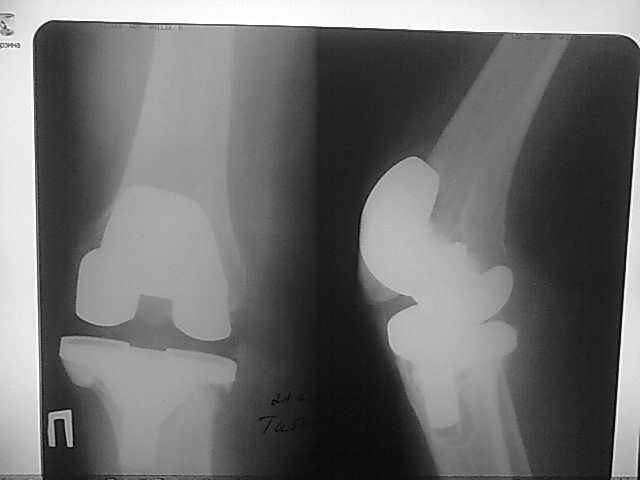

Женщина 1952 г.р., оперирована в 2006, в одной клинике установлен эндопротез правого коленного сустава, через год нестабильность обоих компонентов, доктор выполняет ревизию обычным протезом с задним стабилизатором.

В октябре 2008 - нестабильность, свищ. В другом стационаре все удалено, спейсер с гентамицином, длинный курс антибиотиков.

Коллатеральных связок нет. Собственная связка надколенника цела.

До удаления протеза - выраженная смешанная контрактура.

Планы: Стоит выбор 1) Обычный hinge с цементными ножками, вставками под тибиальным и бедренным компонентами с импакционной костной пластикой аллокостью с применением сеток для удержания трансплантата на tibia; 2) Онкологический hinge - с замещением проксимальной голени и сохранением бедра; 3 - артродез.